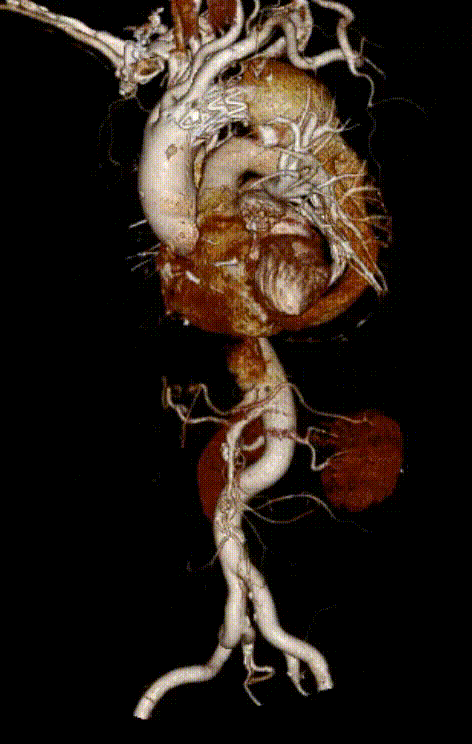

【病例2】主动脉B型夹层,

2016年外院TEVAR术后II型内漏

术后8年随访发现假腔明显扩大,最大直径达96mm,伴胸背疼痛,有手术干预指征。

再干预方案:弹簧圈栓塞分支血管(LSA栓塞),覆膜支架+封堵器+弹簧圈覆盖左肾动脉破口。

修复结果:进入假腔血流明显减少,胸背疼痛症状明显缓解。

二次手术前CTA